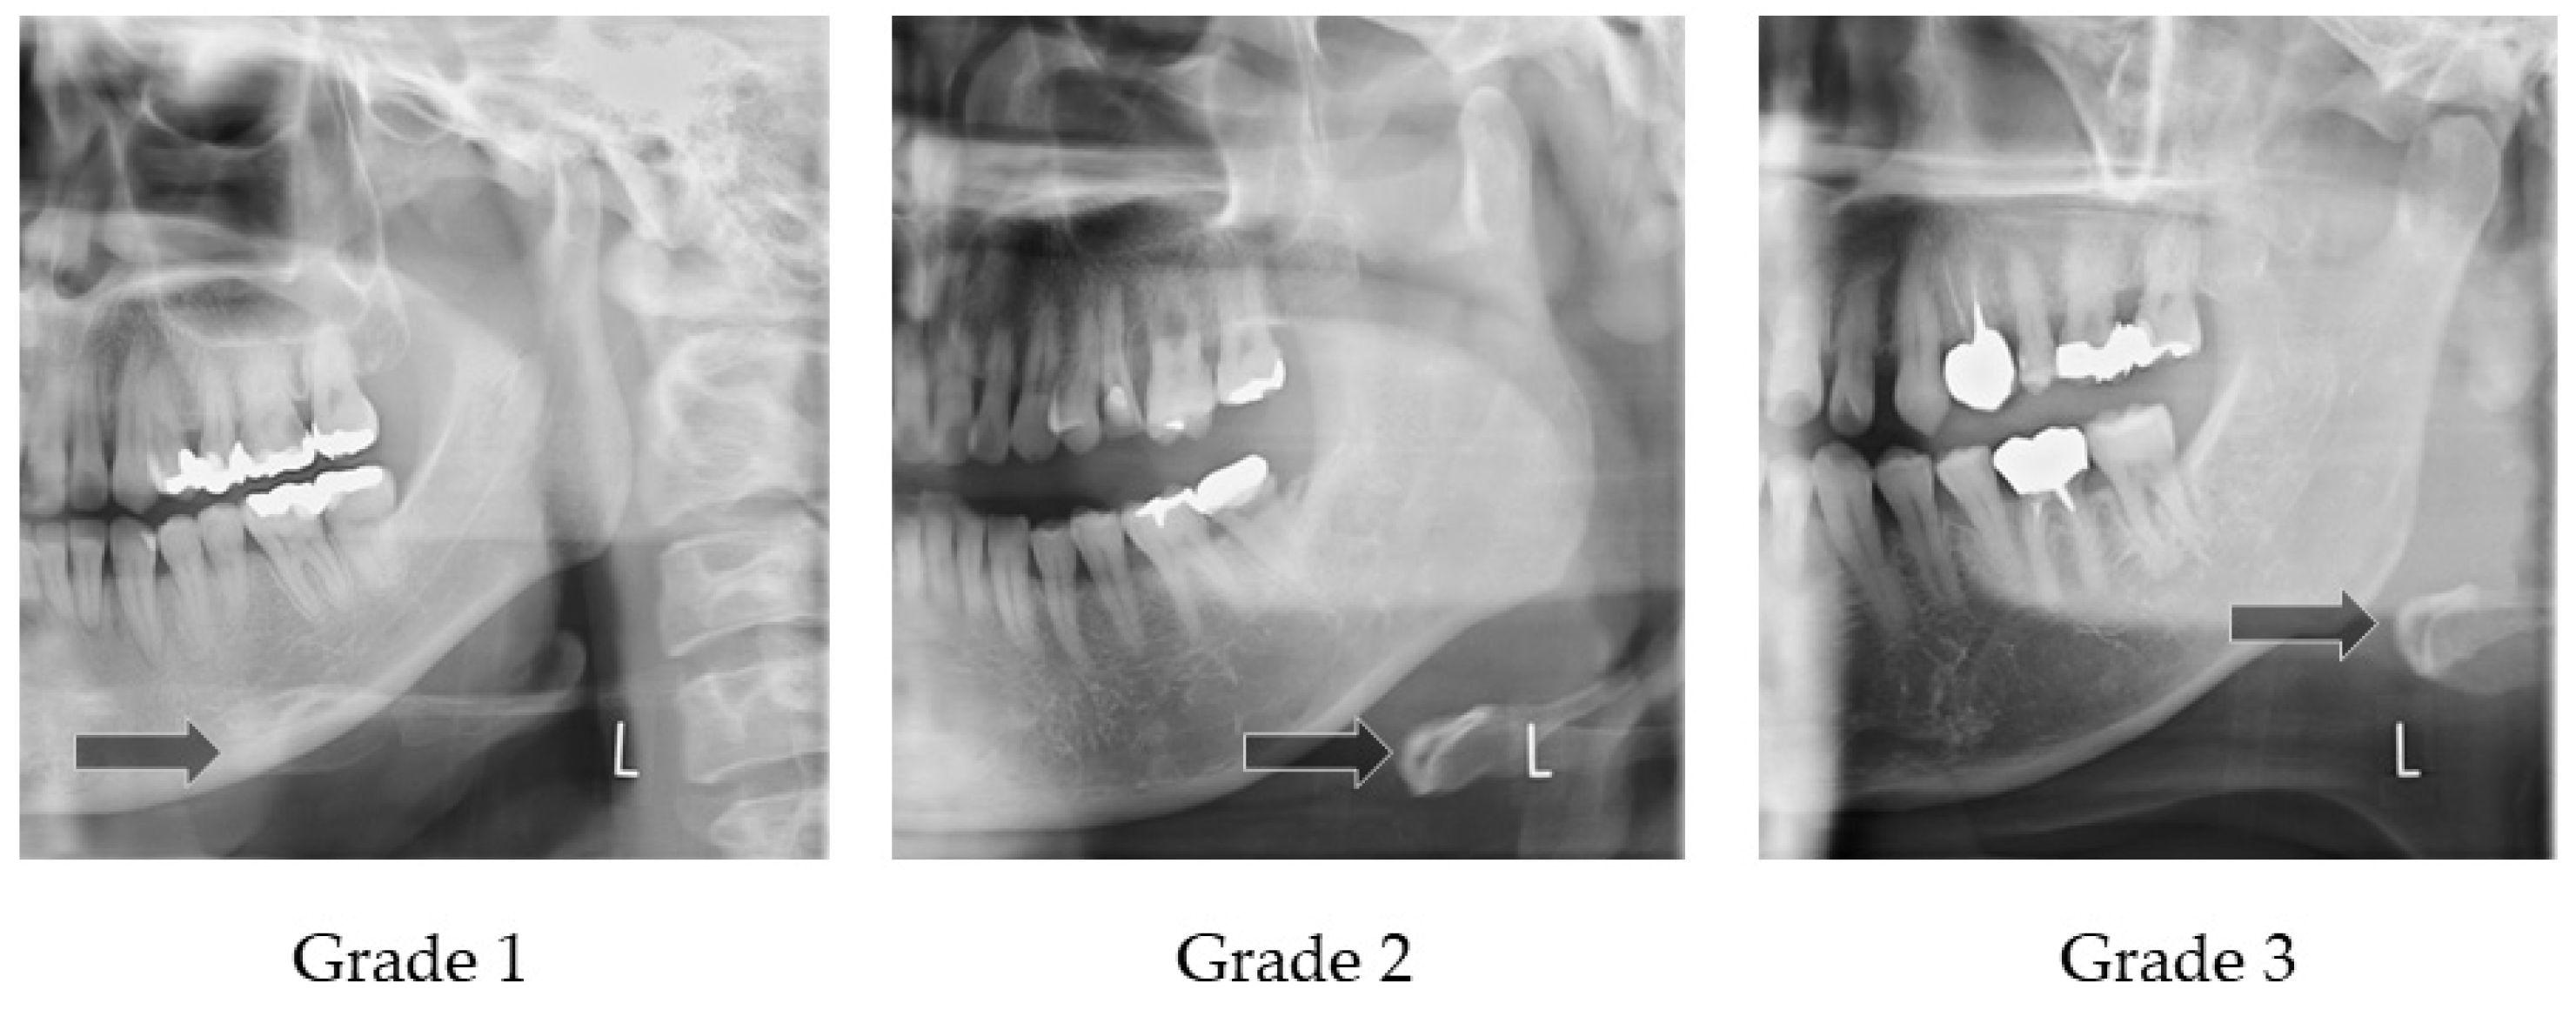

Figure 3 illustrates how to evaluate the position of the horizontal hyoid bone and Figure 4 shows sample images. This method of measurement was taken from Ito et al. [9]. The horizontal position of the hyoid bone was graded based on the anterior point of the hyoid body. Cases in which the hyoid bone was invisible were excluded from this assessment.

Horizontal hyoid bone position. The horizontal hyoid bone position was graded by the position of the anterior point of the hyoid body.

Sample images of horizontal hyoid bone position. Arrow shows the anterior point of the hyoid body.

Six landmarks were defined, as follows:

- The mesial premolar line is the point between the mesial interproximal surface of the first premolar and the vertical border of the mandible until the end of the image. When the first premolar was missing, the distal surface of the canine was used.

- The distal premolar line is the point between the distal interproximal surface of the second premolar and the vertical border of the mandible until the end of the image. When the second premolar was missing, the mesial surface of the first molar was used.

- The premolar area is the area between the mesial premolar line and the distal premolar line.

- The distal molar line is the perpendicular line from the distal interproximal surface of the second molar or the mesial interproximal surface of the third molar to the edge of the image through the lower border of the mandible. When the second molar was missing, the mesial surface of the third molar was used.

- The molar area is the area between the distal premolar line and the distal molar line.

- The posterior area is the area posterior to the distal molar line.

In cases where the relevant tooth or its neighboring tooth was missing, these landmark lines were referred to the maxillary tooth.

Grade 1 is the most anterior point of the hyoid body that is observed in the premolar zone.

Grade 2 is the most anterior point of the hyoid body that is observed in the molar zone.

Grade 3 is the most anterior point of the hyoid body that is observed in the posterior zone.